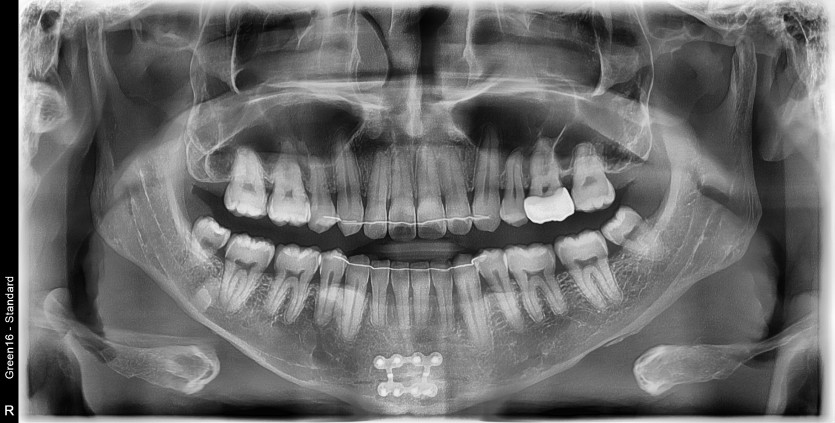

#38 사랑니 발치

구강 외과 전문의가 당일 발치했습니다.